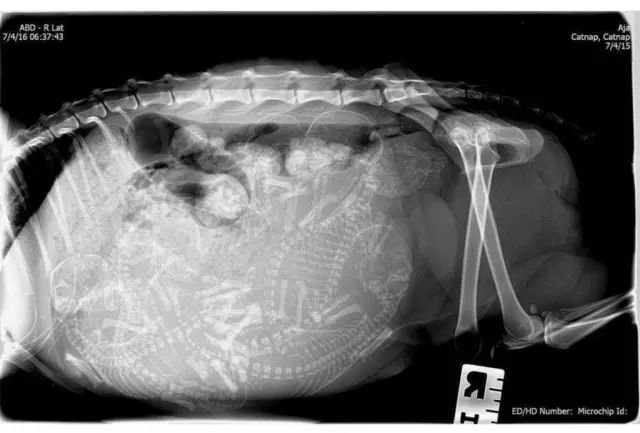

狗狗怀孕x光图片解析

狗狗怀孕x光图片解析,验孕棒图片怀孕图片

17种动物怀孕期间的x光照片,真的太神奇了

怀孕犬从下到上的x光片

怀孕x光照片

狗狗x光